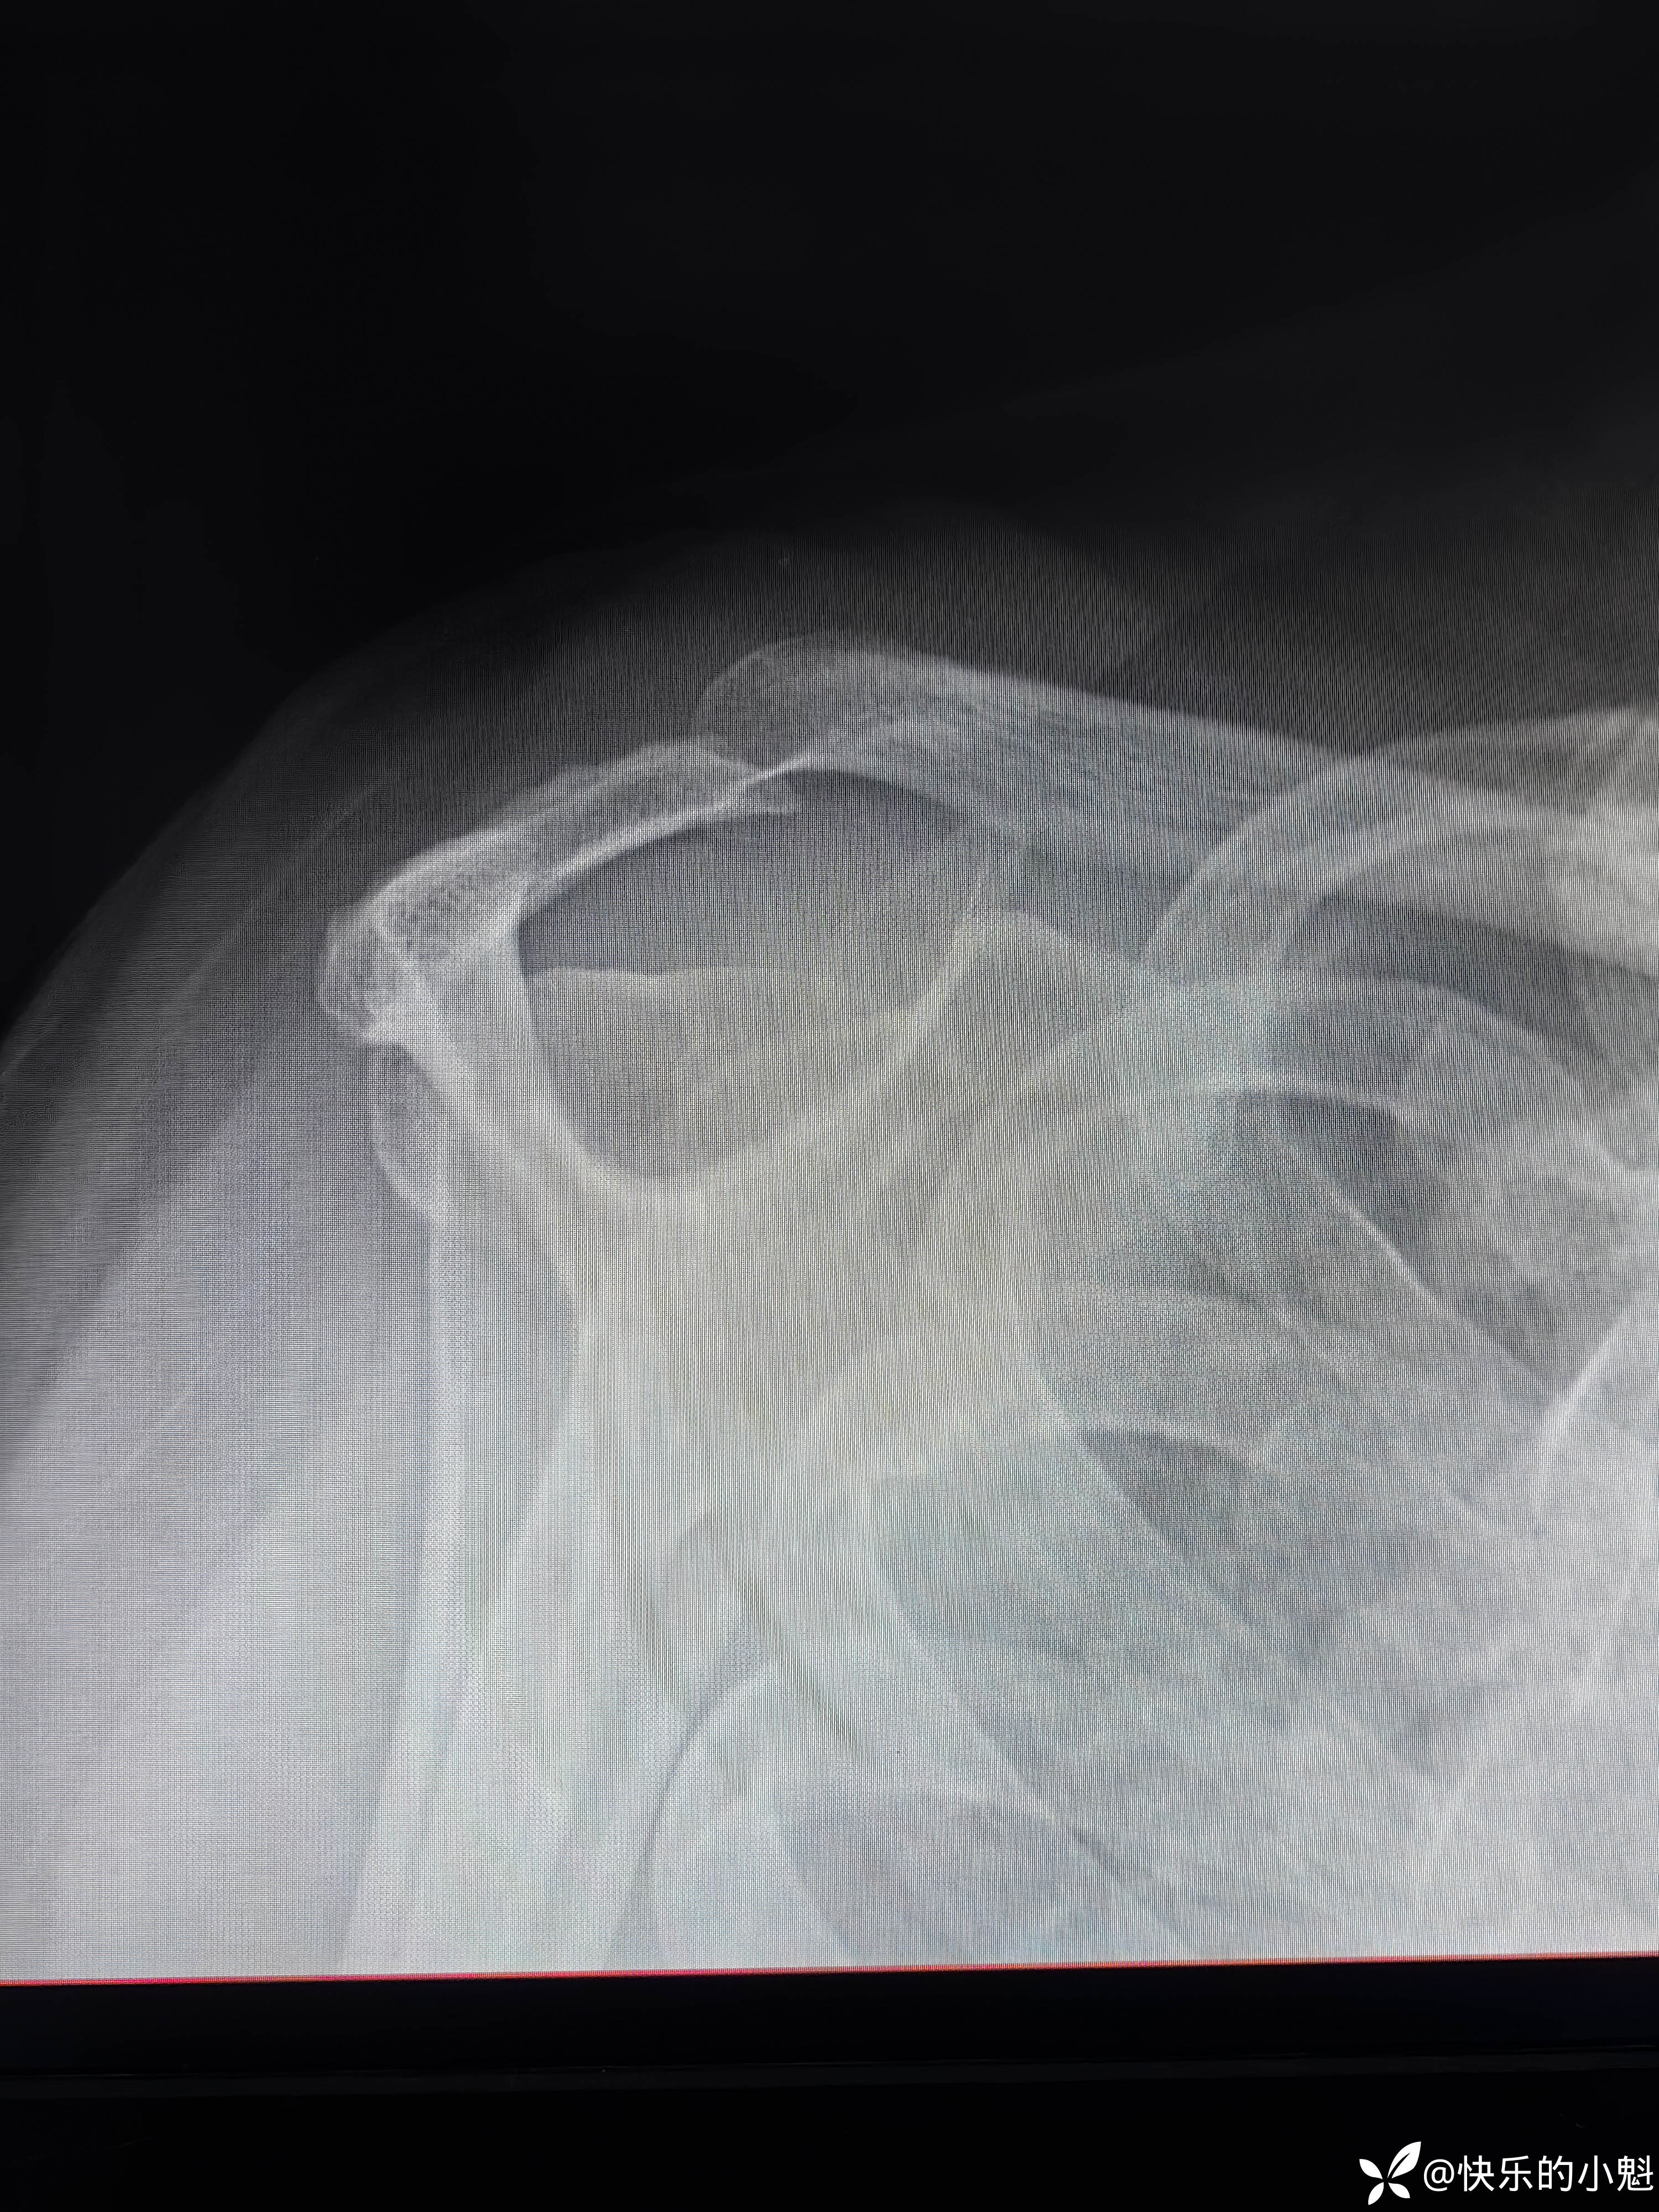

- 右肩X线示:右侧肩峰增生,2型肩峰(见下图)。